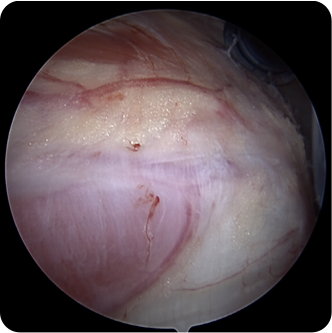

회전근개파열의 여러 모습들

회전근개파열의